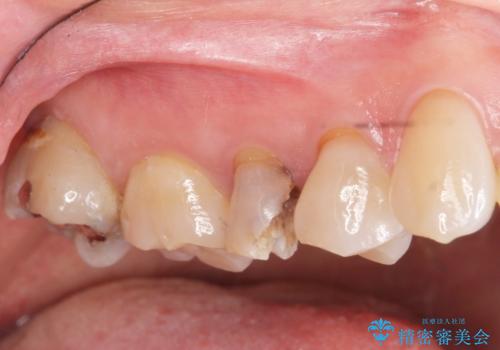

- 大きく歯が欠けてしまった虫歯の治療を希望され来院されました。

虫歯による歯の崩壊で歯を残すことが難しかったので抜歯を行い、インプラント・入れ歯ではなくブリッジによる咬合機能の回復を希望されました。

- 天然歯を削ります

- 硬い素材は天然歯を傷つけてしまう場合があります

- かみ合わせや歯ぎしりが強すぎる方はセラミックが割れてしまう可能性があります